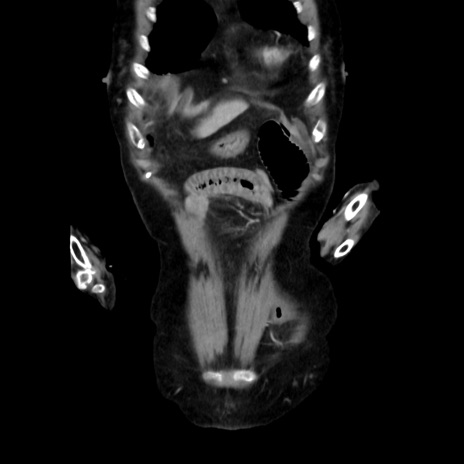

症例40(冠状断像)

【症例】90歳代女性

【主訴】腹痛・嘔吐

【現病歴】 食欲低下、嘔吐があり昨日他院受診。肺炎と診断され入院となる。入院後より腹部全体に圧痛あり。胃管留置され経過みていたが、症状持続するため、

当院転院となる。

【既往歴】胸椎圧迫骨折、胆石症

【身体所見】腹部:中央に激痛あり、圧痛あり、反跳痛不明

【データ】WBC 17100、CRP 18.82

冠状断像